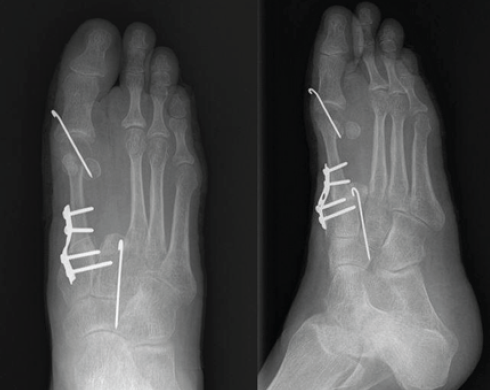

Figure 4: Post-operative X-rays showing semitubular plate fixation for the metatarsocuneiform joint and K-wires in the metatarsophalangeal joint and base of the 2nd metatarsal-cuneiform joint.

A five holed 2.7 mm semitubular plate was used to stabilize the metatarso-cuneiform joint and a K-wire for metatarso-phalangeal joint, the base of second metatarsal was fused with intermediate cuneiform to maintain the arch support (Fig. 5).